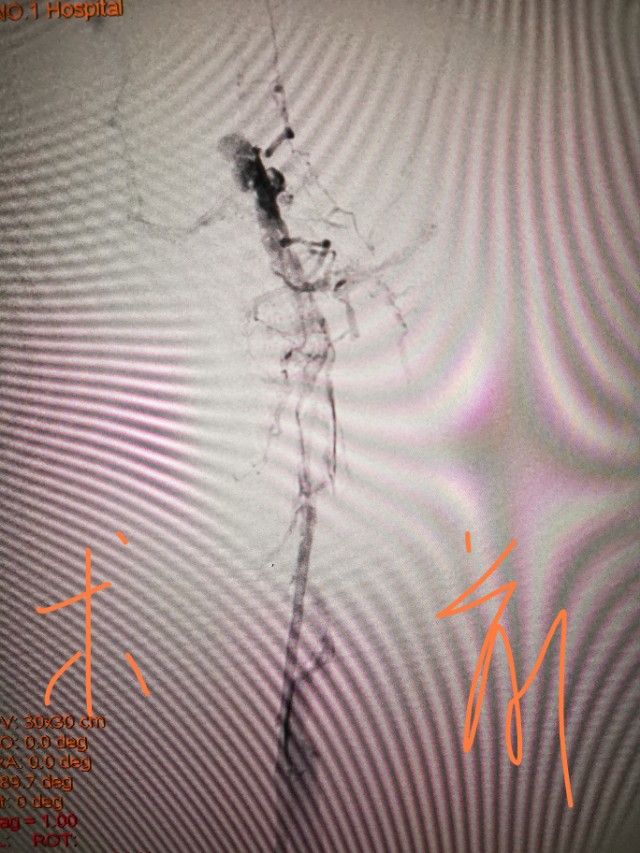

我们可以进行药物治疗和介入治疗,只要病人最近半年没有活动性出血如胃出血和脑出血,我们可以进行抗凝治疗。抗凝最大的风险是出血和血栓脱落,出血我们可以监测凝血时间,防治肺动脉栓塞,我们可以放滤器保护肺动脉。介入治疗主要是对有血栓的静脉进行血栓抽吸、球囊扩张、支架植入等。